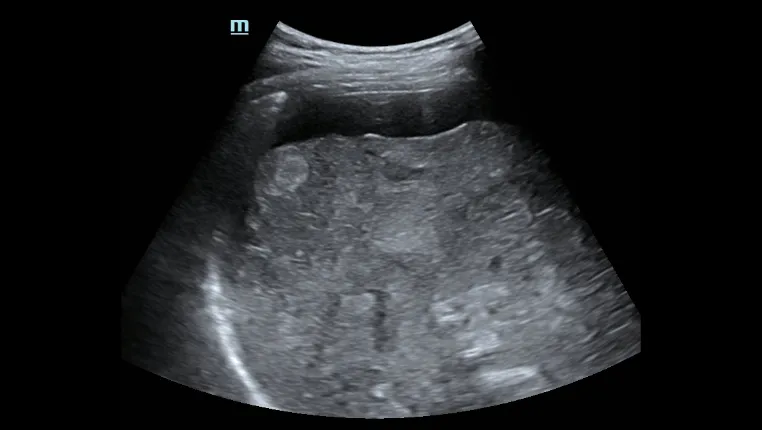

Асцит печени

Оценка морфологии печениЭргономичный дизайн